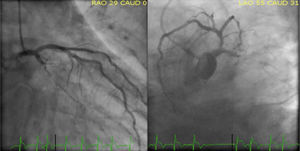

On day seven, percutaneous MV repair was performed, using a right femoral vein approach (24Fr), with deployment of 3 clips (MitraClip NT), successfully (final MR 1+), without complications (transmitral mean gradient in the end of the procedure 5 mmHg) (Figure 4). Within 24 h of the procedure we successfully removed IABP support, and we managed to wean off non-invasive ventilation.